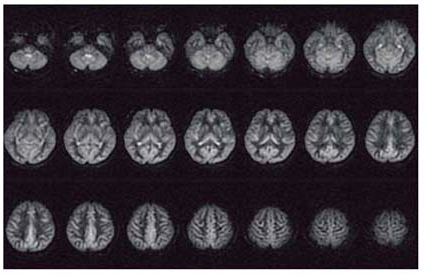

図3 pCASL法を用いた3T MRIによる全脳のパーフュージョン画像

3D FSEをベースとしたシーケンスを用いることで,全脳を歪みなくカバーすることが可能となる。